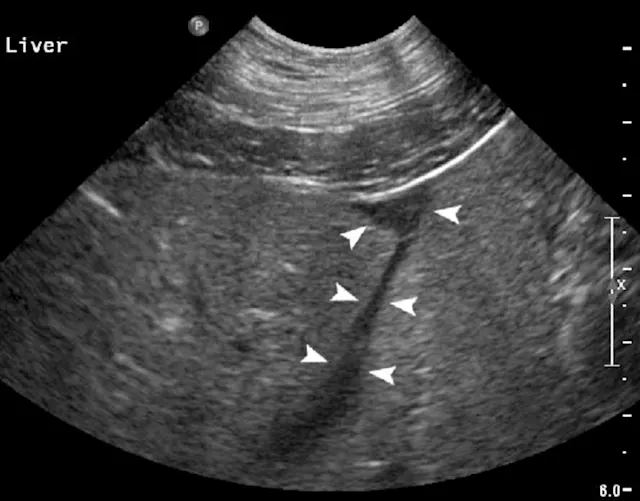

Biopsy needle tract within the patient after firing and just before removing the biopsy device (B). Post-biopsy hemorrhage often collects between hepatic lobes as seen in this image (white arrow heads) (C). The echogenic fluid represents acute hemorrhage. Color flow Doppler post-biopsy ensures there is no persistent hemorrhage in the peritoneal space (D). Power Doppler imaging is the most sensitive form of Doppler to detect the presence or absence of blood flow.

Step 8: Inspect for Hemorrhage

Every time a biopsy is made, the site should be inspected for evidence of hemorrhage. Hemorrhage will often collect around and between liver lobes as seen in 5C between the arrowheads. Color (or power) Doppler ultrasound may help visualize active bleeding as seen in 5D. Once the patient is no longer bleeding, the patient can be recovered. Observe the patient closely in the postoperative period for clinical evidence of blood loss. Serial ultrasound examinations may be beneficial for discovering progression hemorrhage. If the patient continues to bleed, a blood transfusion may be needed. It is usually beneficial to obtain packed-cell volume readings at 15 and 45 minutes post-biopsy to ensure that active bleeding has stopped. An external elastic belly wrap can be helpful in preventing further hemorrhage.